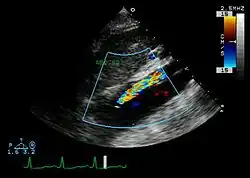

Ultrasound

The transesophageal echocardiogram (TEE) is a good test in the diagnosis of aortic dissection, with a sensitivity up to 98% and a specificity up to 97%. It has become the preferred imaging modality for suspected aortic dissection. It is a relatively noninvasive test, requiring the individual to swallow the echocardiography probe. It is especially good in the evaluation of AI in the setting of ascending aortic dissection and to determine whether the ostia (origins) of the coronary arteries are involved. While many institutions give sedation during transesophageal echocardiography for added patient comfort, it can be performed in cooperative individuals without the use of sedation. Disadvantages of TEE include the inability to visualize the distal ascending aorta (the beginning of the aortic arch), and the descending abdominal aorta that lies below the stomach. A TEE may be technically difficult to perform in individuals with esophageal strictures or varices.

-

Aortic dissection with an intramural hematoma as seen on TEE